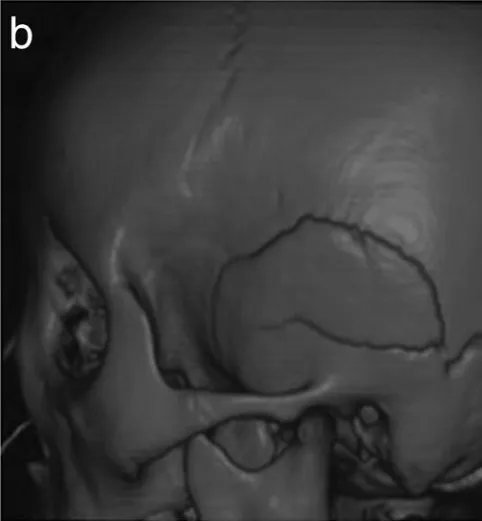

图b:3D骨CT显示多发性颅骨骨折